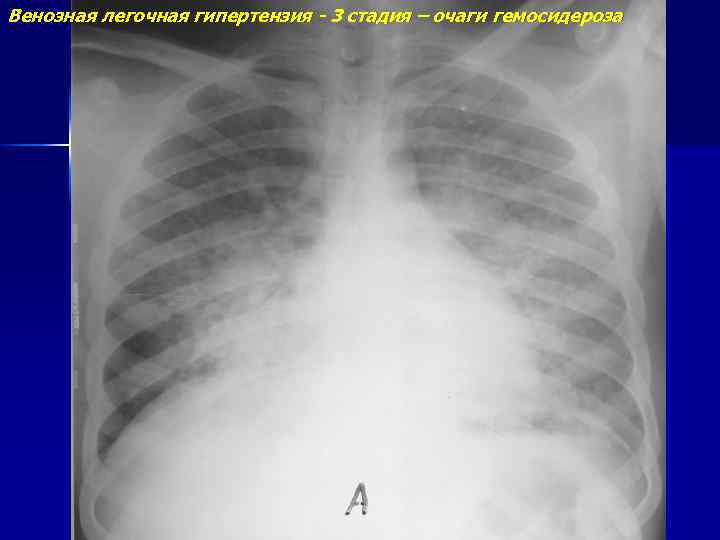

Венозная легочная гипертензия - 3 стадия – очаги гемосидероза